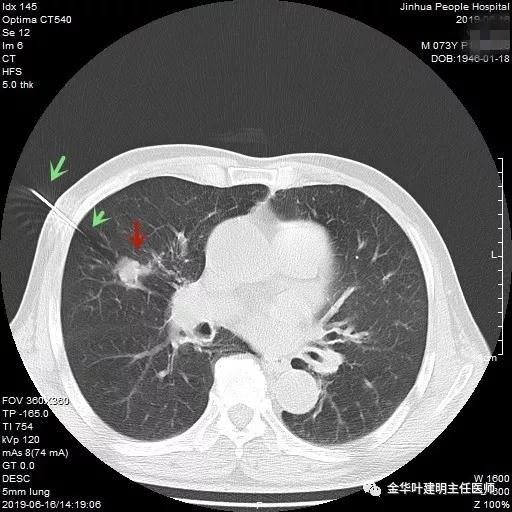

武义的吴某,今年已经73岁了,患有慢性支气管炎与肺气肿多年,每到天气转凉就要胸闷、气急及咳嗽、咳痰发作,严重时还有喘憋症状,每年都要住院1-2次。今年4月份的时候吴某又因慢支急性发作来我院呼吸内科住院。常规检查时发现右肺上叶有一实性结节,约1.5厘米大小,有毛刺及浅分叶,考虑肺癌可能性大,医生建议其行肺穿刺活检。当时图片如下:

吴某不同意肺穿刺,咳嗽咳痰好转后就出院了。此后于今年6月份回院复查,仍然住在内科,这次想通了,同意肺穿刺,结果病理果然是肺癌,是低分化鳞癌。因为吴某与本院一院级领导是同村的,便让我去会诊。我觉得虽然从病灶来看可以手术,纵隔内也无明显转移的肿大淋巴结,相关检查也无远处转移证据。但患者年纪较大,平时有慢支与肺气肿,发作时还有喘憋症状,肺功能也示重度混合型通气功能障碍,MVV重度降落。询问吴某,平时一口气走上3楼是有困难的,所以行右肺上叶切除术后出现呼吸功能不全的概率还是比较高的,手术存在较大风险。争取手术也是为争取根治以至得到较长期生存的机会。若同意手术,也要家属与患者都十分理解,并对术后需要呼吸机辅助以及无法脱离呼吸机支持都有充分的思想准备。而若放弃手术,则主要是免疫治疗及放化疗,其中放化疗对肺功能也有一定影响,且无法达到根治的目的。我当时告诉吴某儿子,要开,做好术后出现呼吸功能衰竭的准备,且不能责怪我的同事和我本人;若暂不手术,也可回当地考虑保守治疗;当然也可先戒烟、锻炼肺功能、使用支气管扩张剂等改善肺功能,较短时间内再回院复查肺功能,再争取手术。吴某当时办理了出院手续,也没有与我们确认是否考虑手术。下面是当时6月份时候的片子以及肺穿刺情况:

绿色箭头示穿刺针,红色箭头示肿瘤